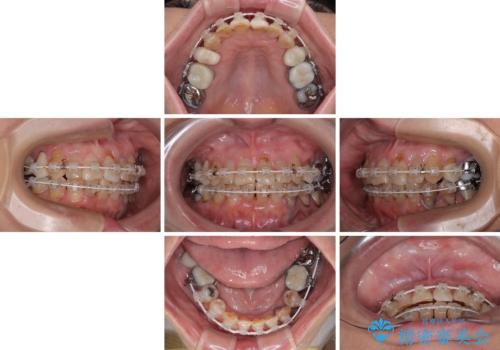

- 矯正装置

- 審美装置

- 治療期間

- 2年1ヶ月

- 治療回数

- 30回以上